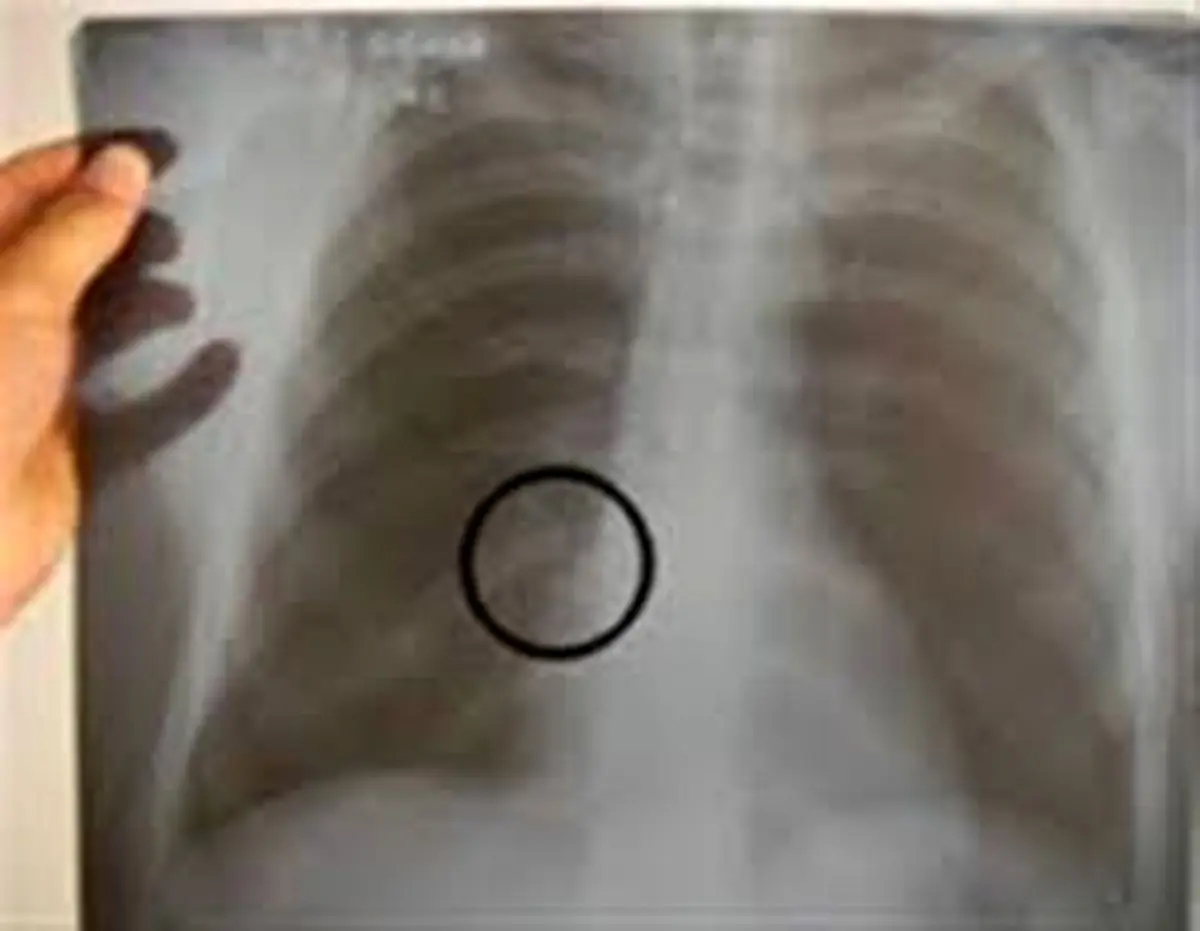

یکی از موارد شایع در تصادفهای ساختگی، شکستگی دندان است. این افراد با علم به اینکه دندانهای قدامی دیه زیادی دارند، بهطور ساختگی اقدام به شکستن دندانهای قدامی میکنند. دیه هر یک از این دندانها معادل 5درصد دیه کامل انسان است. آنها در محیطی امن با استفاده از ابزار تخصصی این کار را انجام میدهند و در نهایت باعث سقوط دندان شده و دیه سنگینی میگیرند. مورد دیگر شکستگی در اندامهاست. این افراد پیش از عملیکردن نقشهشان درباره میزان دیه هر عضو تحقیق میکنند. مثلا میدانند که دیه شکستن دندهها حدود 8درصد دیه کامل است و معمولا به دندهها آسیب میزنند.